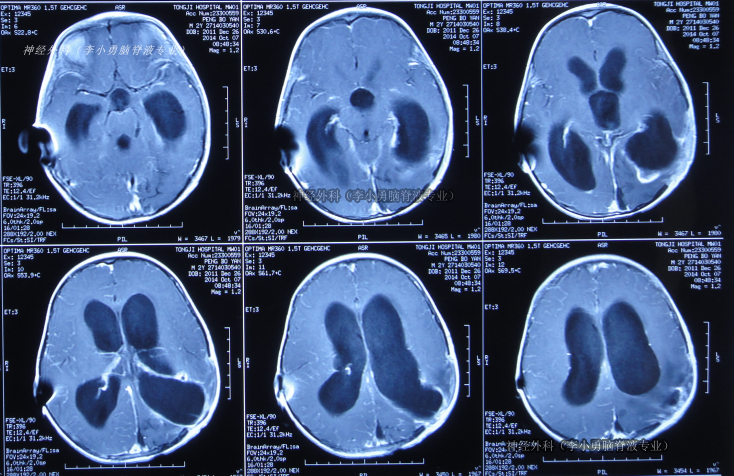

菱脑融合畸型

神经内科-神经内科

努力学English 关注

南充卫生学校2026年01月09日 23:58 20阅读 0评论 0点赞